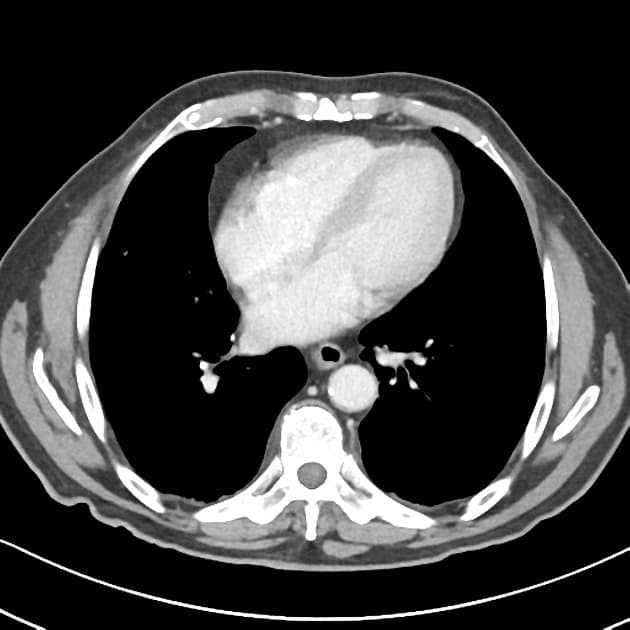

Có các dấu hiệu viêm hoạt động ảnh hưởng đến đoạn cuối ruột non và đoạn đầu ruột già: dày thành ruột (mural thickening), phù (edema), hạn chế khuếch tán (restricted diffusion) và tăng quang sau tiêm thuốc đối quang ở đoạn cuối 30 cm của ruột non và manh tràng (cecum). Mô hình tăng quang có dạng mục tiêu (targetoid), với tăng quang ở lớp niêm mạc và thanh mạc. Trong đoạn ruột bất thường này, có các đoạn ngắn không bị tổn thương, tại đó thấy các túi nhỏ ở bờ đối mạc tràng (anti-mesenteric border sacculation). Phía trên đoạn bệnh lý, có hiện tượng giãn nhẹ. Ngoài ra, ghi nhận sự tăng sinh mỡ ở vùng hạ vị phải, làm tách biệt các quai ruột bị bệnh khỏi các quai ruột còn lại trong ổ bụng. Có thể thấy hình ảnh hình thành đường rò giữa hồi tràng và manh tràng liền kề. Có nhiều hạch bạch huyết viêm trong mạc treo ruột non. Không thấy hình ảnh (no evidence of) tổn thương ở ruột non đoạn gần hoặc các đoạn khác của đại tràng. Các đoạn ruột viêm có nhu động giảm. Không thấy hình ảnh dịch tự do hoặc ổ dịch trong ổ bụng hay tiểu khung.

Hình ảnh cho thấy các đặc điểm điển hình của bệnh viêm hoạt động, bao gồm dày thành ruột và phù, tăng quang dạng lớp (layering enhancement), hạn chế khuếch tán, mỡ bao quanh (fat wrapping), và tạo túi giả dọc theo bờ đối mạc tràng. Ngoài ra, có bằng chứng của bệnh lý xuyên thành (transmural disease) với hình thành đường rò giữa hồi tràng và manh tràng.

- "Tổn thương khu trú với các tổn thương bỏ cách (skip lesions) và tạo túi ở bờ đối mạc tràng giúp phân biệt bệnh Crohn với các bệnh viêm ruột khác."